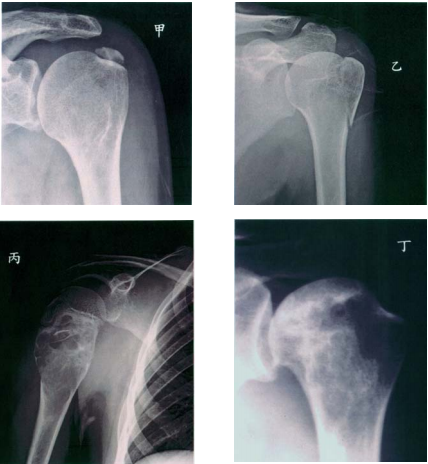

60 下列四個肱骨頭的病變中,何者屬於急性之傷害?

(A)甲 (B)乙 (C)丙 (D)丁